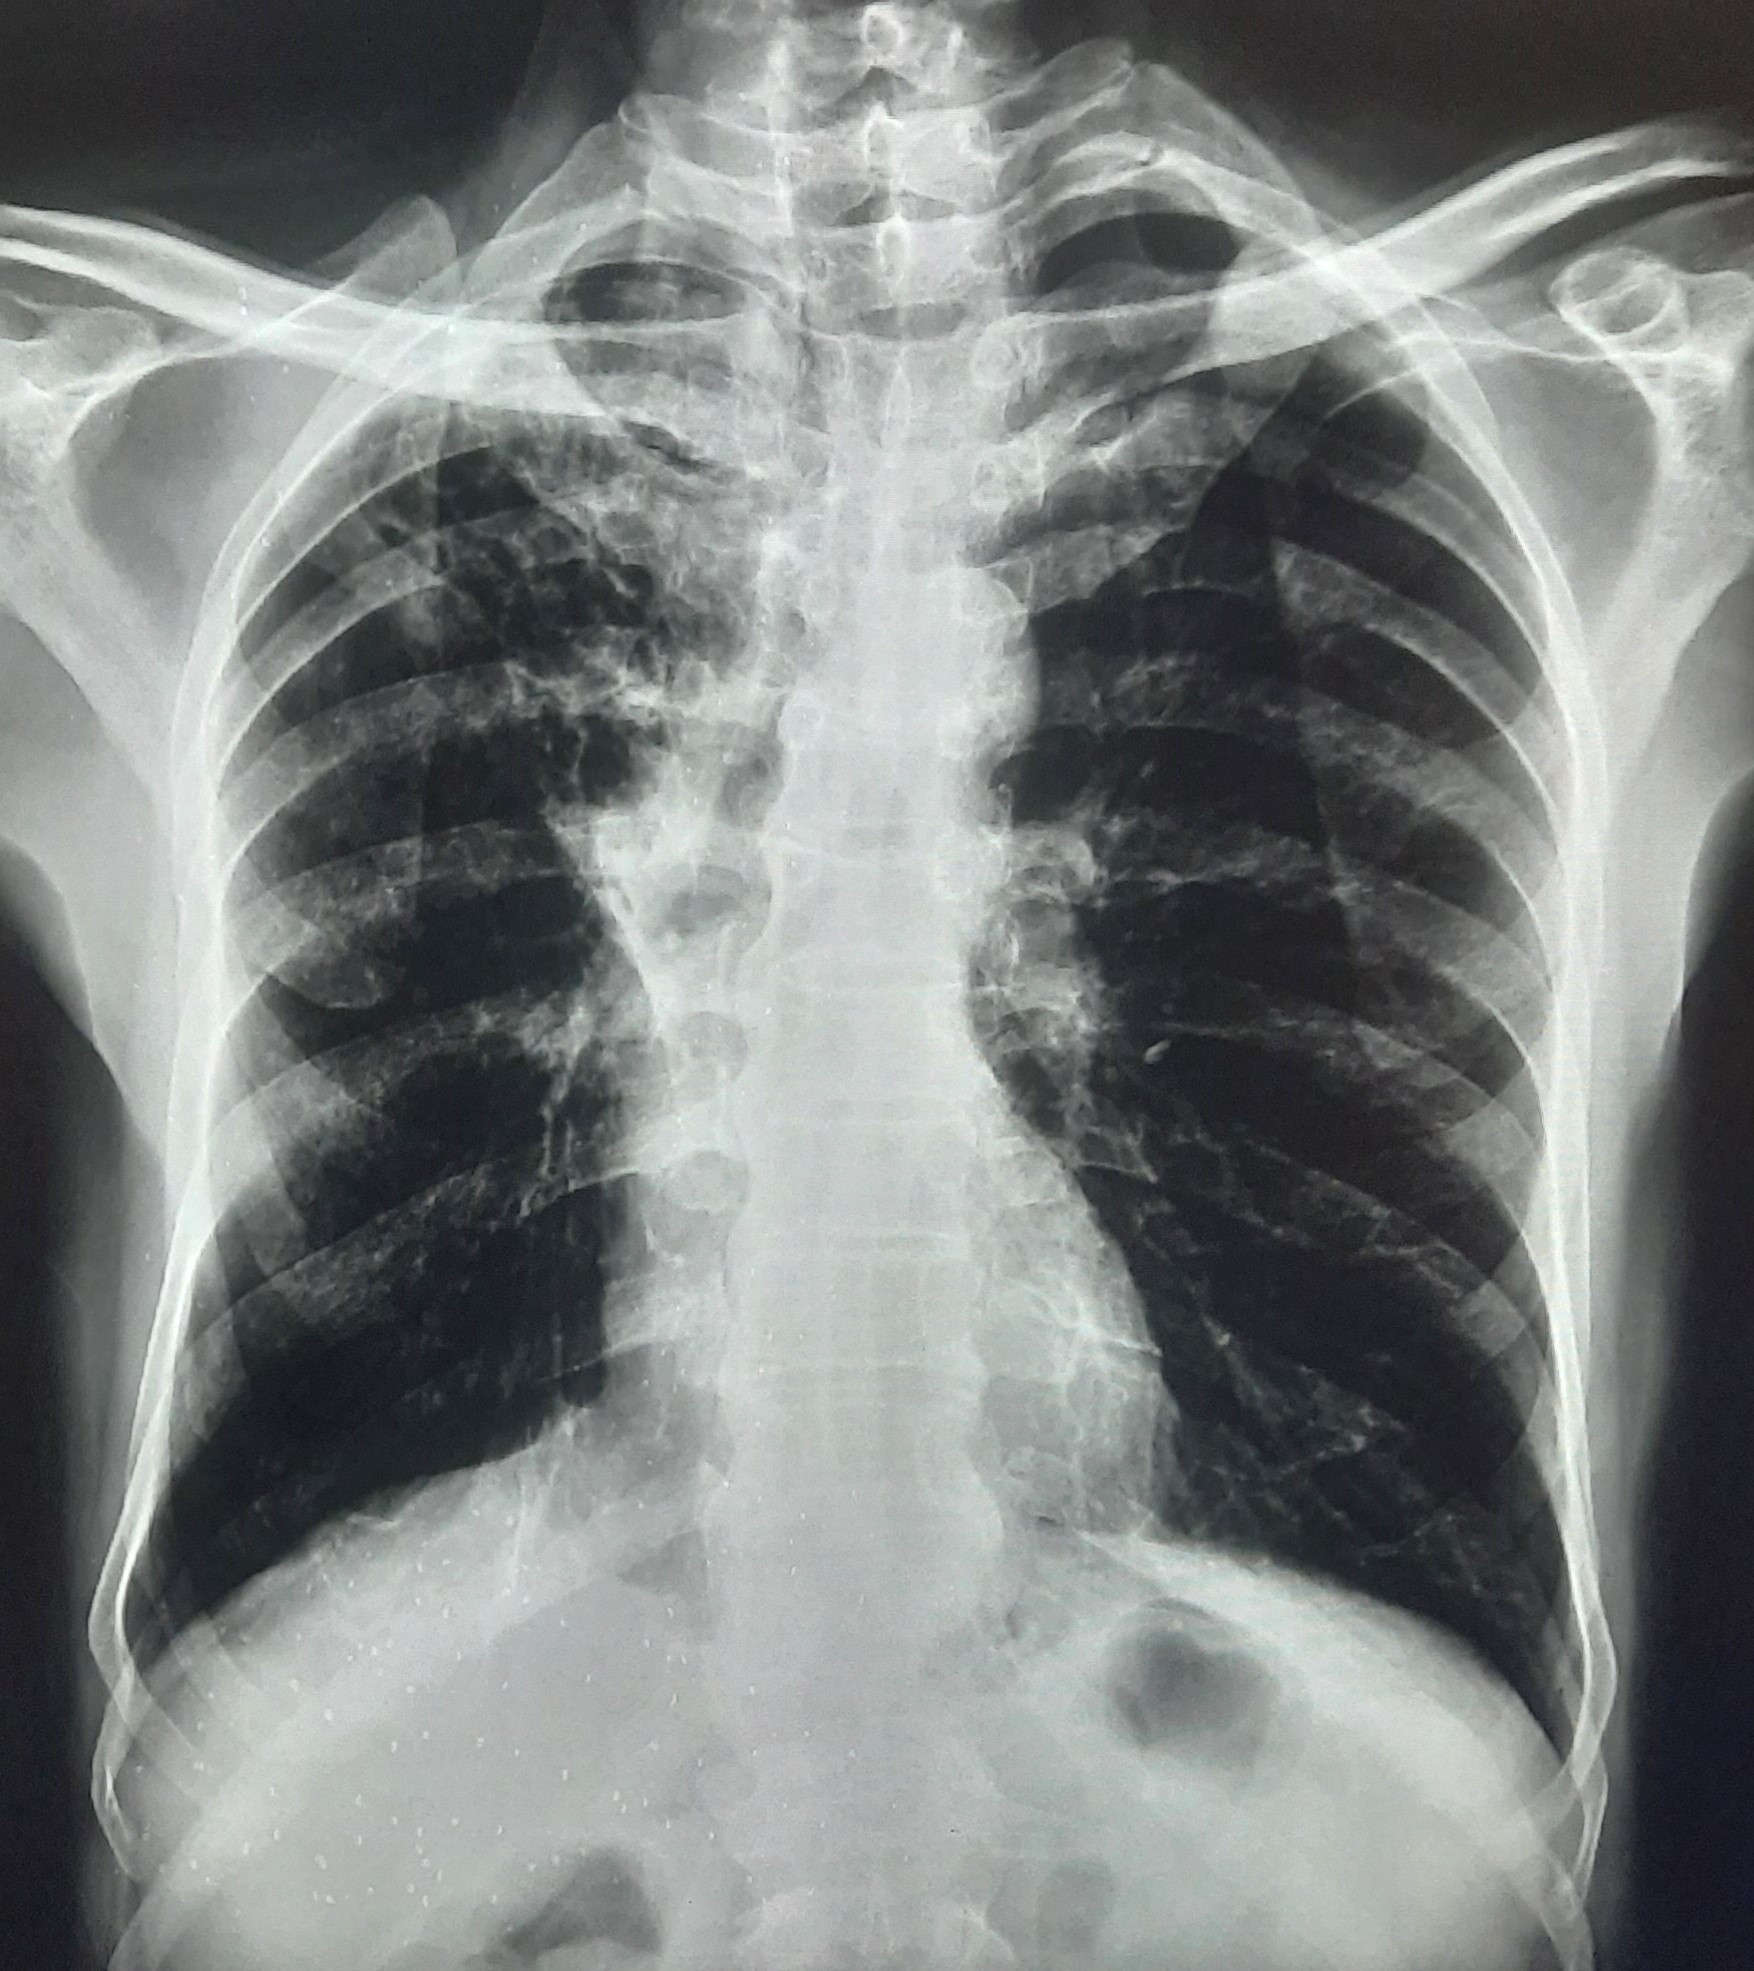

| 297 | IGGMC, Nagpur, Nagpur | P2 | 29-4175 | Sabina Parveen | Consent taken on Paper | 23 Yrs. |

Provisional Diag : PTB Reactivation

Final Diag : ? |

TB Case (Confirmed) | Bilateral Middle Lower Zone Pulmonary TB | Abnormality visible on x-ray |